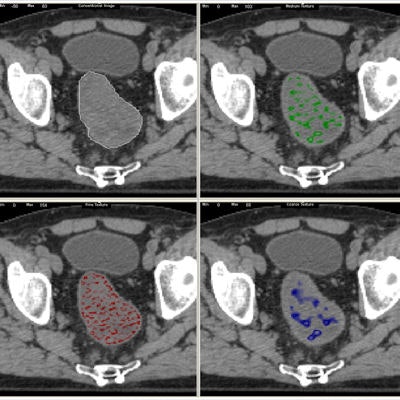

TexRad breaks down tumor images into different components separately -- fine structures separately, medium structures separately, and the large coarser structures separately, and it breaks down the images and quantifies the different distributions or patterns via the histogram analysis.

In analyzing the textures to try to predict the aggressiveness of a lesion, "It's actually emulating what radiologists are trying to do but giving objectivity to the practice rather than subjectivity," he said. Only using the software, time after time, the same ROI, and the same region of interest will get the same numbers and the same marker of heterogeneity.